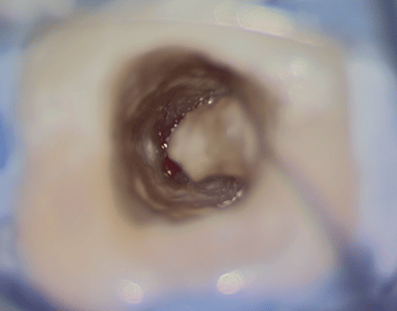

このような状態になるまで、根管の中を綺麗にしていきます。実はこの作業は非常に難しいです。図の右の凸部は歯なのですが、この裏には歯槽骨(骨)が入り込んでいて、薄皮1枚みたいな状態です。これに穴をあけると、また別の問題が生じます。